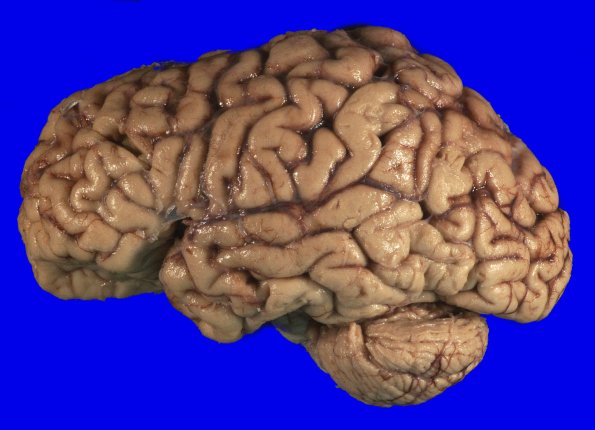

5A2 (Case 5) Gross_2

There is mild atrophy of the frontal, temporal, and parietal lobes.